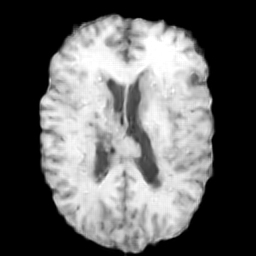

Brain MRI

We also evaluate our method on the BraTS-Reg (Baheti et al. 2021) dataset, which provides pre-operative and follow-up MRI scans for patients with diffuse glioma. The dataset includes multimodal MRI sequences (T1, T2, FLAIR, and T1 contrast-enhanced) collected longitudinally for each subject. To mitigate inter-scan variability caused by different acquisition protocols, histogram standardization (Nyul, Udupa, and Zhang 2000) is first applied to the pre-operative and follow-up T1 and T2 scans. We then perform Z-normalization, rescale the intensity to the range, and crop the scans to a resolution of . The pre-operative and follow-up scans are rigidly aligned using the SimpleITK registration framework (Yaniv et al. 2018). For experiments, 160 subjects in BraTS-Reg are split into training and testing sets with a 7:3 ratio and the central eleven slices are extracted to form a dataset with 1232 training pairs and 528 testing pairs.

4.5 Experiment Results on Brain MRI

To further demonstrate the effectiveness of TraceTrans, we additionally evaluated the model on Brain MRI dataset. The quantitative results are shown in Table 2 and TraceTrans performs best in SSIM, MAE, NMI and slightly worse than MUNIT in PSNR. Since the difference between TraceTrans and MUNIT on PSNR is less than 5% of either standard deviation, then this difference is negligible. TraceTrans shows significant SSIM improvement while matching MUNIT’s PSNR and achieving the lowest MAE, demonstrating balanced excellence in both structural and textural translation. Qualitative results are illustrated in the second row of Figure 4, the image generated by our model is visually best similar to the reference image.